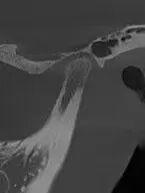

治疗前1

治疗前2